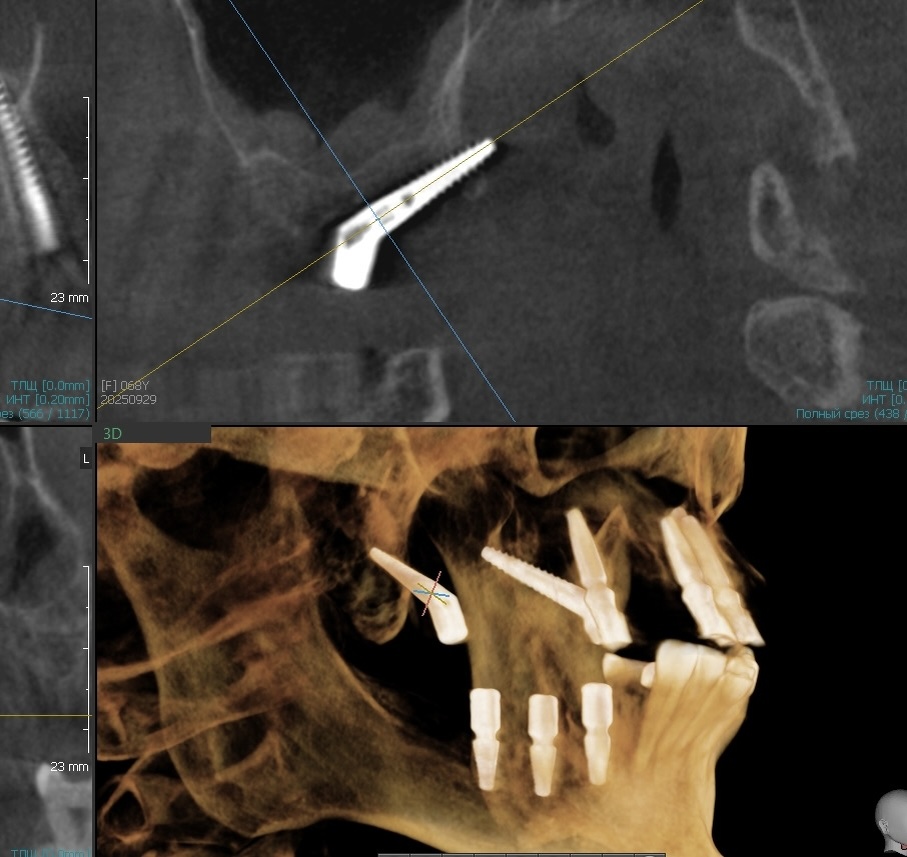

Шесть имплантатов на верхней челюсти, два из них птеригоидные. На прошлой неделе в понедельник провели тотальную операцию, а сегодня, в среду на следующей неделе, сдали классный временный протез длительного ношения.

Начали несколько месяцев назад с установки двух птеригоидных имплантатов.

Дали им время прижиться без нагрузки - иногда это важно для таких длинных конструкций, которые уходят в крыловидный отросток клиновидной кости. Но, иногда, установка происходит сразу всех имплантатов и сразу же все нагружаются протезом.

Птеригоидные имплантаты - это особая история, о которой я уже много раз писала. Это классического вида имплантаты, которые фиксируются в крыловидном отростке клиновидной кости, очень плотной и стабильной. Позволяют обойтись без синус-лифтинга и дают опору в самых дальних отделах челюсти.

Шахты выходят в проекции седьмых зубов. Это значит, что даже на временном протезе можем дать пациенту полноценный зубной ряд до семёрок. Еси можем) Помним про то, что всё всегда индивидуально.

• сама операция - установка имплантатов строго по плану, без импровизации и без сюрпризов. Аппарат КЛКТ в клинике и после установки имплантатов производится контроль их заглубления. Всё очень чётко у нас.